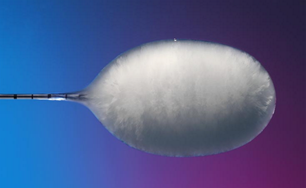

Cryoablation

La cryoablation détruit la tumeur par le froid (jusqu’à −40 °C), en créant un véritable « glaçon » autour de la lésion.

Ses avantages :

meilleure tolérance à proximité des vaisseaux,

visualisation précise de la zone traitée,

douleur souvent moindre.

Elle est particulièrement intéressante pour certaines lésions pulmonaires complexes.